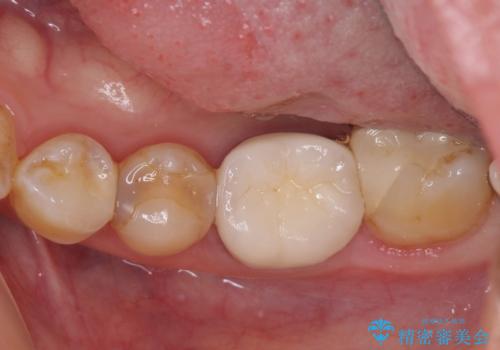

- 冷たいものがしみるとのことで来院された患者様です。

診査を行った結果、第一小臼歯にある樹脂の詰め物(コンポジットレジン)と歯の境目が痛みの原因であることが分かりました。

また、隣接する第二小臼歯も虫歯になっていることも分かったため、2歯を同時に治療するにしました。

下顎の目立つ位置であるため、セラミックインレーによる修復治療を行うこととしました。